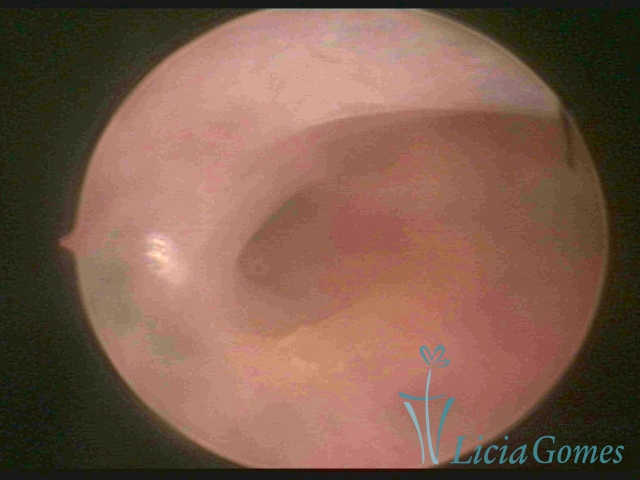

Unicornuate uterus

It presents a tubular cavity with an impaired intracavitary space, resembling the shape of a banana, whose the narrowest edge contains the tubal ostium. The endometrium is compatible with the menstrual cycle and the cervical canal is normal, in structure and trophism.